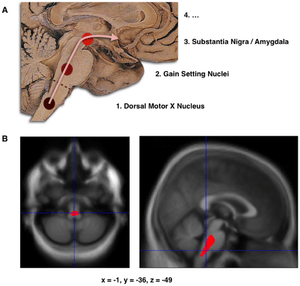

B. Localization of the area of significant brain volume reduction in initial PD compared with a group of participants without the disease in a neuroimaging study, which concluded that brainstem damage may be the first identifiable stage of PD neuropathology[56]